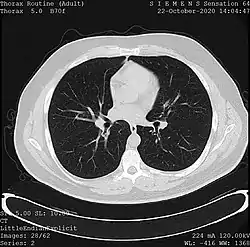

Tomography

Tomography is the imaging by sections or sectioning. The main such methods in medical imaging are:

- X-ray computed tomography (CT), or Computed Axial Tomography (CAT) scan, is a helical tomography technique (latest generation), which traditionally produces a 2D image of the structures in a thin section of the body. In CT, a beam of X-rays spins around an object being examined and is picked up by sensitive radiation detectors after having penetrated the object from multiple angles. A computer then analyses the information received from the scanner's detectors and constructs a detailed image of the object and its contents using the mathematical principles laid out in the Radon transform. It has a greater ionizing radiation dose burden than projection radiography; repeated scans must be limited to avoid health effects. CT is based on the same principles as X-Ray projections but in this case, the patient is enclosed in a surrounding ring of detectors assigned with 500–1000 scintillation detectors[13] (fourth-generation X-Ray CT scanner geometry). Previously in older generation scanners, the X-Ray beam was paired by a translating source and detector. Computed tomography has almost completely replaced focal plane tomography in X-ray tomography imaging.